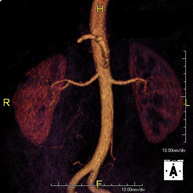

Prueba diagnóstica no invasiva que consiste en el estudio de la arteria aorta abdominal, obteniendo imágenes de alta definición anatómica mediante el empleo de un campo electromagnético y ondas de radio (con un emisor y un receptor). Es indispensable el uso de contraste paramagnético (Gadolinio). Sin embargo, no utiliza radiación ionizante. La calidad de las imágenes permite realizar reconstrucciones en 2D y 3D. Está indicado en aquellos pacientes con enfermedad vascular (aterosclerosis), estudio de aneurismas, en estudios pre-quirúrgicos de lesiones adyacentes a la aorta abdominal como "mapa" vascular, etc. - Angio RM Aorta-ilíaca

Prueba diagnóstica no invasiva que consiste en el estudio de la arteria aorta abdominal, obteniendo imágenes de alta definición anatómica mediante el empleo de un campo electromagnético y ondas de radio (con un emisor y un receptor). Es indispensable el uso de contraste intravenoso paramagnético (gadolinio). Sin embargo, no utiliza radiación ionizante. La calidad de las imágenes permite realizar reconstrucciones en 2D y 3D. Está indicado en aquellos pacientes con enfermedad vascular (aterosclerosis), estudio de aneurismas, en estudios pre-quirúrgicos de lesiones adyacentes a la aorta abdominal como "mapa" vascular… - Angio-RM Aorta iliaca